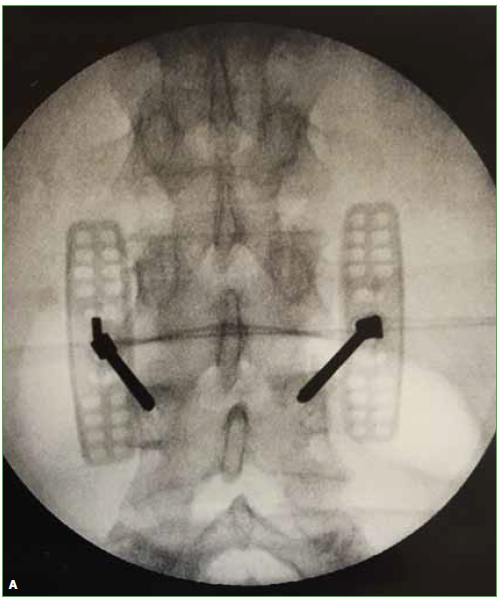

Las hernias discales intraesponjosas vertebrales o nódulos de Schmörl consisten en una herniación o una extrusión del núcleo pulposo del disco intervertebral a través del platillo vertebral hacia el cuerpo adyacente. Suelen asociarse a deformidades vertebrales, como la enfermedad de Scheuermann, o a enfermedades reumáticas, como la espondilitis anquilopoyética. En general, son hallazgos casuales y cuadros asintomáticos; son pocos los casos publicados de nódulos sintomáticos. Su aparición estaría relacionada con un platillo vertebral debilitado por traumatismo o estrés repetido. Cuando el nódulo es agudo o reciente, puede ser difícil diferenciar la degeneración benigna de una infiltración maligna o una infección. Presentamos un caso inusual de un nódulo de Schmörl doloroso en un hombre sin antecedentes de relevancia, que enmascaró una lesión metastásica de carcinoma pancreático a nivel lumbar. Se realiza una revisión bibliográfica. ABSTRACTIntraosseous disc herniation –or Schmörl nodes (SN)– are a herniation or prolapse of the nucleus pulposus of the intervertebral disc through the vertebral plate and into the adjacent vertebral body. They are usually associated with vertebral deformities, suchas Scheuermann’s disease, or rheumatic diseases, such as ankylopoietic spondylitis. In general, they are spontaneous and asymptomatic findings, and there are only a few reported cases of symptomatic nodes. The etiology is supposedly related to a weakened spinal plate due to trauma or repeated stress. When the node is acute or recent, it can be difficult to differentiate a benign degeneration from a malignant infiltration or infection. In this paper, we discuss the unusual case of a painful Schmörl node in a man with no relevant history and a masked metastatic lumbar spinal tumor originated from pancreatic cancer. We performed a literature review.Descargas